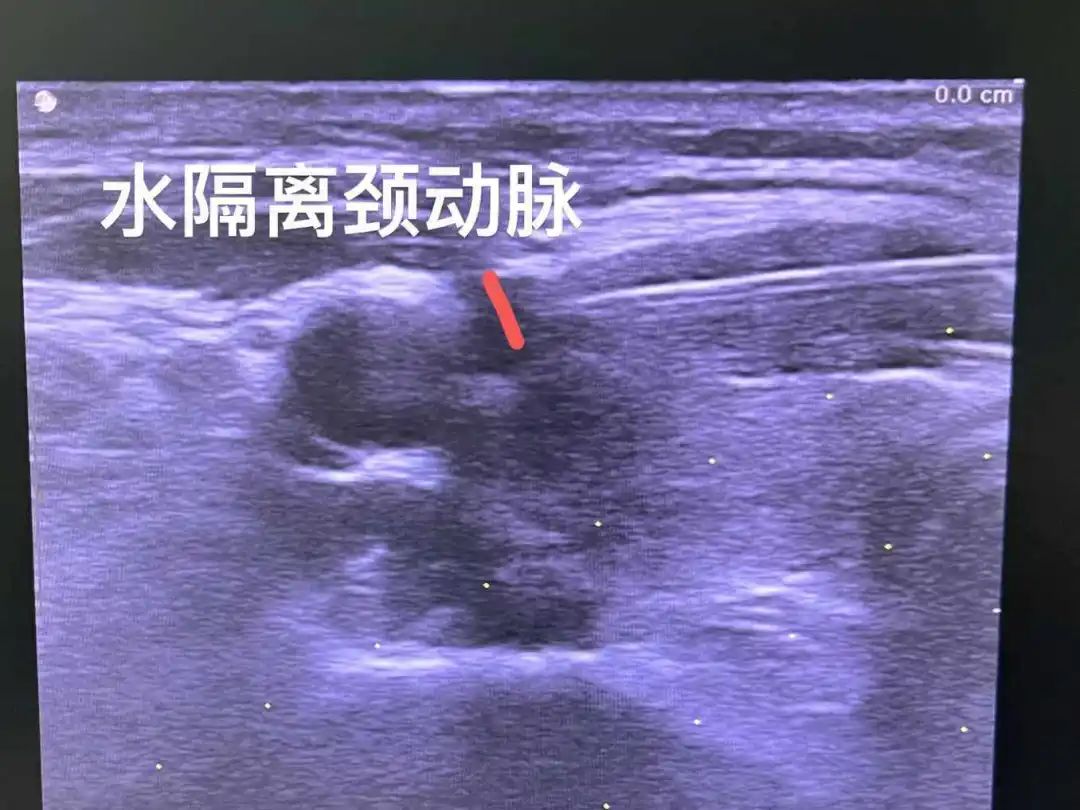

▲建立“防火墙”——先注射盐水形成水隔离带,把颈动脉推开,再行紧靠颈动脉的甲状腺结节消融。

水隔离技术主要包括人工腹水、人工胸水和局部注水,或上述三种技术联合。超声引导下水隔离技术主要是利用了水的高比热容特性,在实时超声引导下利用经皮穿刺针(PTC)把生理盐水注射到预定部位,能非常安全地在需要消融的部位与重要结构或器官之间形成一道液体“保护屏障”,达到肿瘤完全消融灭活且不损伤邻近器官及组织的效果。

水隔离法是利用水在肿瘤与邻近组织间形成隔离带,增大治疗组织与周围组织的间隙,达到必要的操作间距,避免损伤周围其他组织从而导致并发症发生的一种措施。2003年,Farrell等最早应用水隔离于射频消融肾肿瘤,以降低肠道的损伤,证实其是一种有效保护周围脏器的辅助技术。